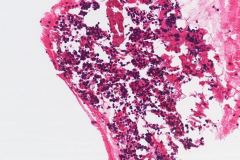

Specimen Type: FNA of Station 7 Lymph node, Diff-Quik and Papanicolaou Stained smears, ThinPrep® Non-Gyn cytology, Formalin-Fixed Cell Block

Cytologic Diagnosis: Positive for Malignant Cells, Metastatic Carcinoma of Breast Origin. The malignant cells are positive for GATA3, AE1/AE3 and estrogen receptor. P40, TTF-1 and Napsin A are negative.

Biopsy / Pathologic Diagnosis: Metastatic Adenocarcinoma consistent with patient’s known history of a breast cancer primary. Immunohistochemical stains including a GATA3 and TTF-1 were used in evaluation of this material. The neoplastic cells show strong and diffuse expression of GATA3 and are negative for expression of TTF-1, supporting a metastasis from the patient’s known breast primary. Immunohistochemical stains for estrogen receptor and progesterone receptor were both positive and HER2 was negative.

Ductal breast carcinoma specimens are highly cellular and consist of a variety of cell arrangements. The cells will commonly be seen as poorly cohesive clusters, some isolated single cells, and rare sheets of cells. These specimens will have enlarged and hyperchromatic nuclei that are eccentrically placed and often protruding from the cytoplasm. The chromatin has a bland appearance, ranging from finely to coarsely granular, with prominent, irregularly shaped nucleoli. Myoepithelial cells sitting on top of or lining the ductal breast cells are helpful in determining if the specimen is benign and should not be present in IDC specimens. The background of IDC is usually clean, but inflammation, blood, and granular debris may be observed.1,14 Immunohistochemistry (IHC) markers that can be used to stain for ductal breast carcinoma are Ki-67, p63, CK5/6, ER, Mammaglobin, GCDFP-15, E-Cadherin and GATA3. Double staining for cytokeratin, smooth muscle myosin heavy chain, Calponin, and/or p63 is helpful for determining if myoepithelial cells are present in the specimen.1,15 In the current case study, the patient’s specimen presented with marked cellularity consisting of a population of both 3-dimensional clusters of cells and many dyshesive single cells. In the smaller 3-dimensional clusters, some of the cells can be seen forming glandular structures and some look as if they are molded together. The nuclei are enlarged, eccentrically placed, and have a mix of both smooth and irregular nuclear contours. The cells all have high N/C ratios and there is a moderate amount of anisonucleosis. The chromatin has a predominantly hyperchromatic appearance, is finely granular and large prominent nucleoli can be observed. The cytoplasm is scant, has well-defined cytoplasmic borders, and is finely vacuolated. Mucinous vacuoles in the cytoplasm can be seen in the larger 3-dimensional clusters of cells. Crush artifact and necrosis can be observed in the background.